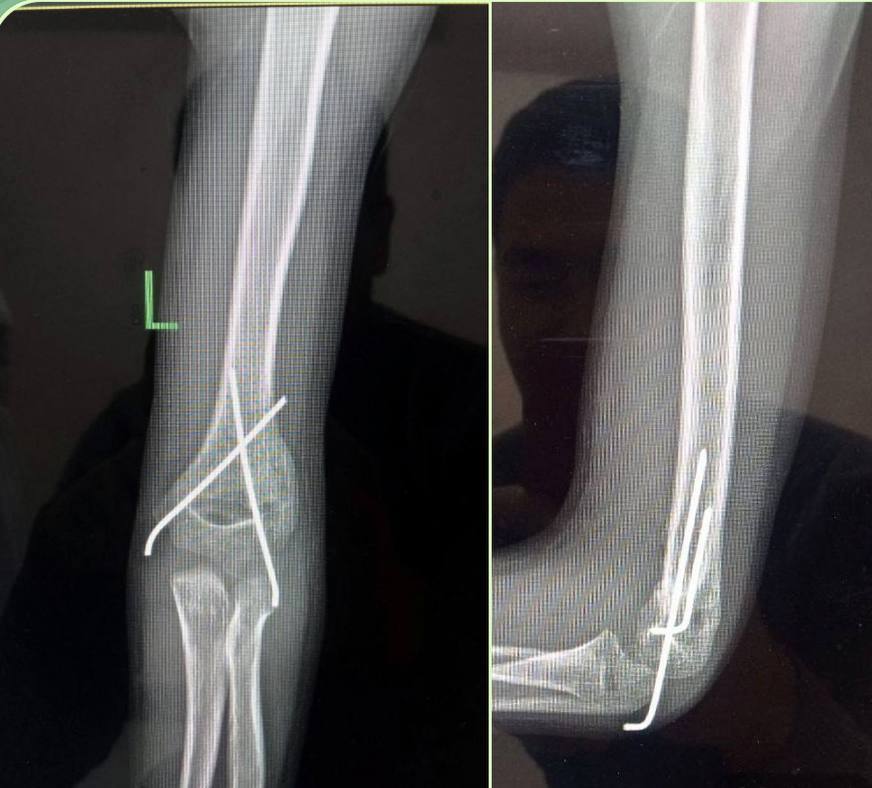

Bloklovchi intramedulyar osteosintez

Operatsiyadan keyingi kuniyoq yura olasiz

Teri kesmalarisiz osteosintez

Yopiq repozitsiya va osteosintez

Mini invaziv osteositez